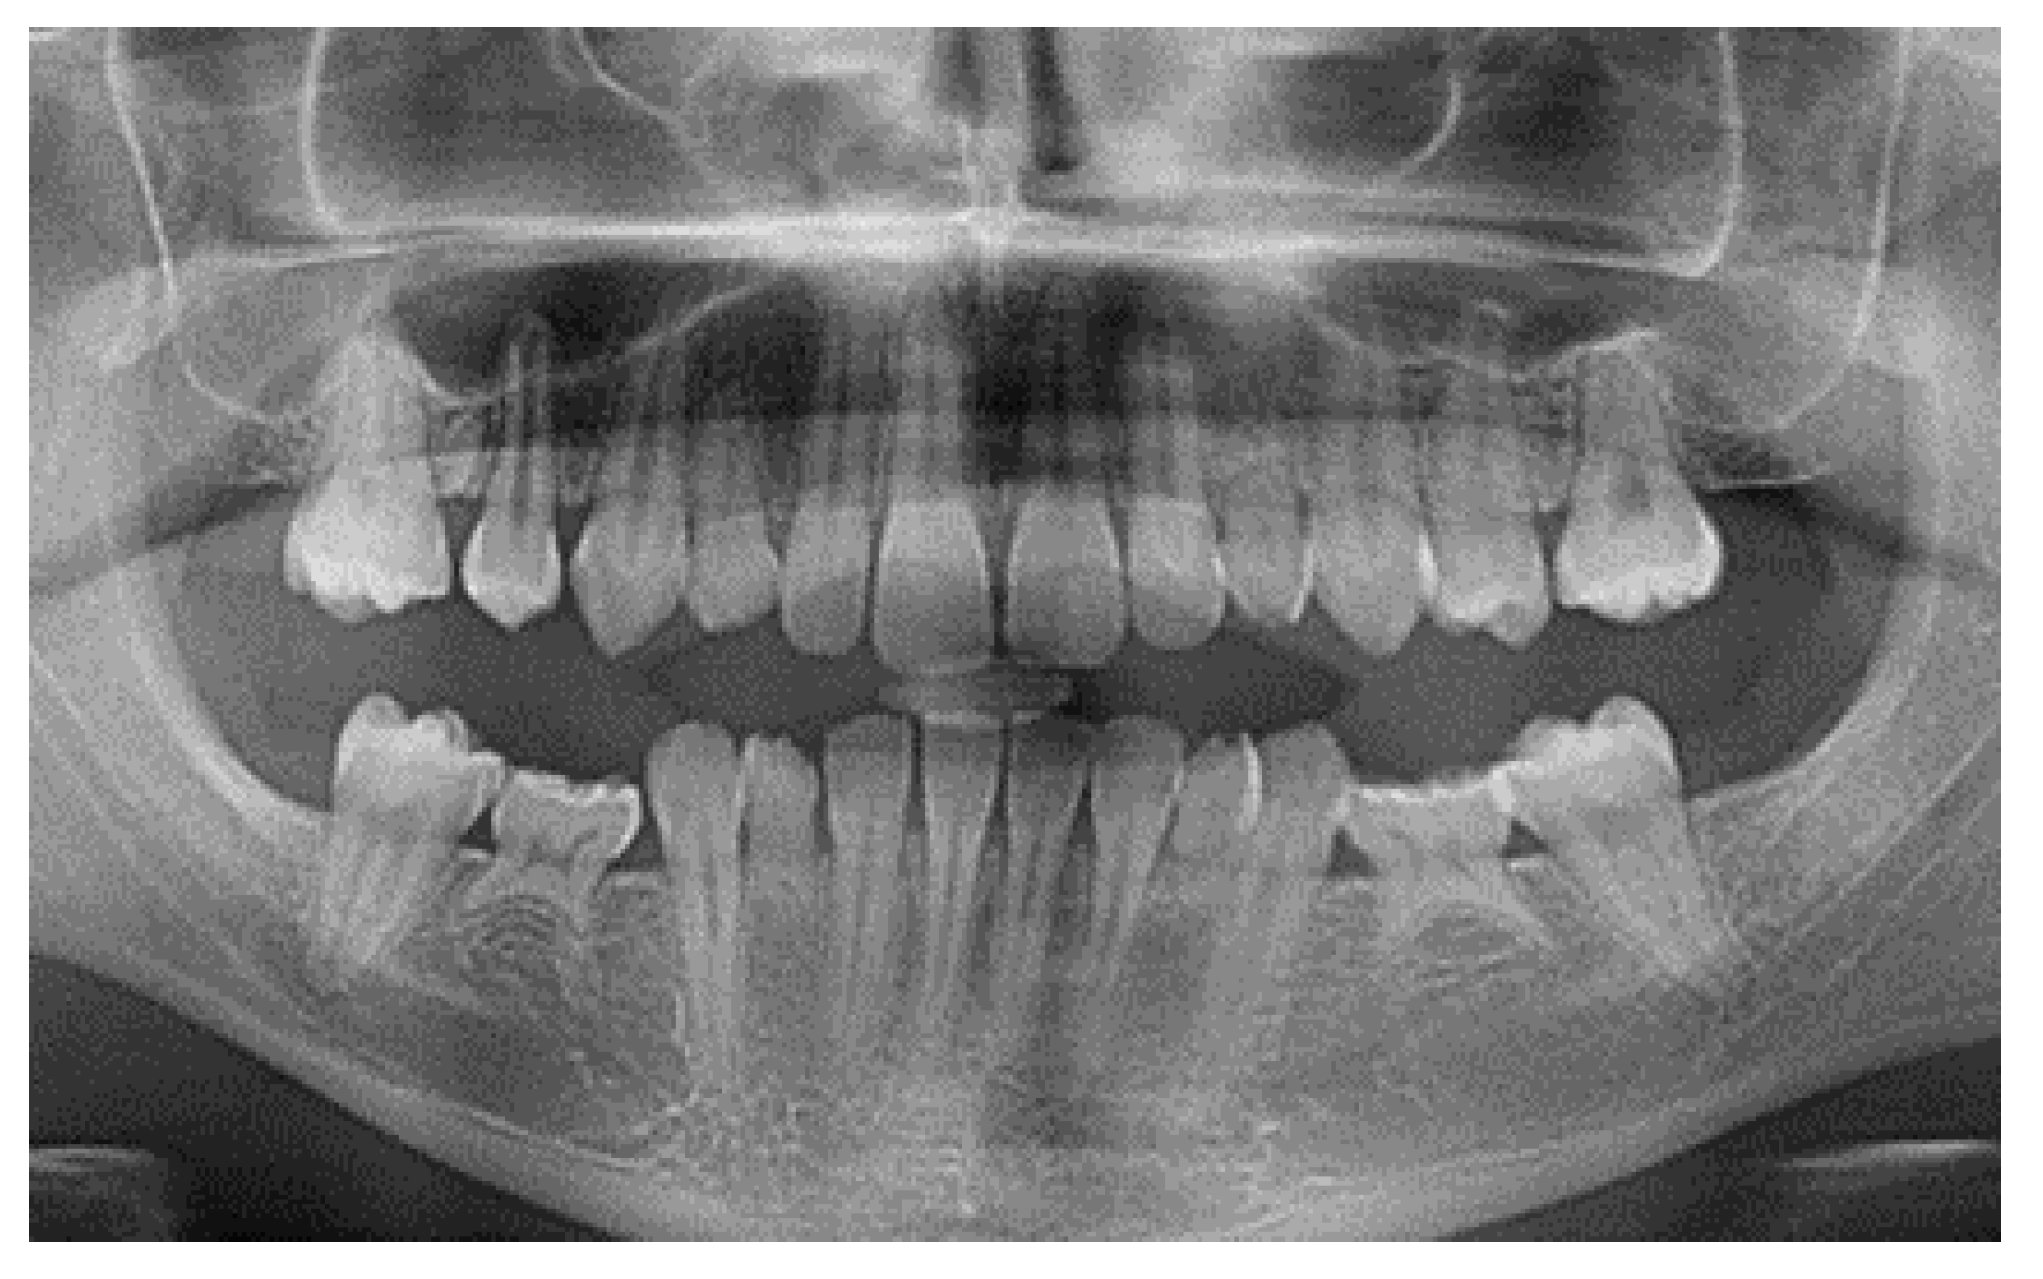

- Case 1:

- Case 2:

- Case 3:

- Case 4:

- Case 5: